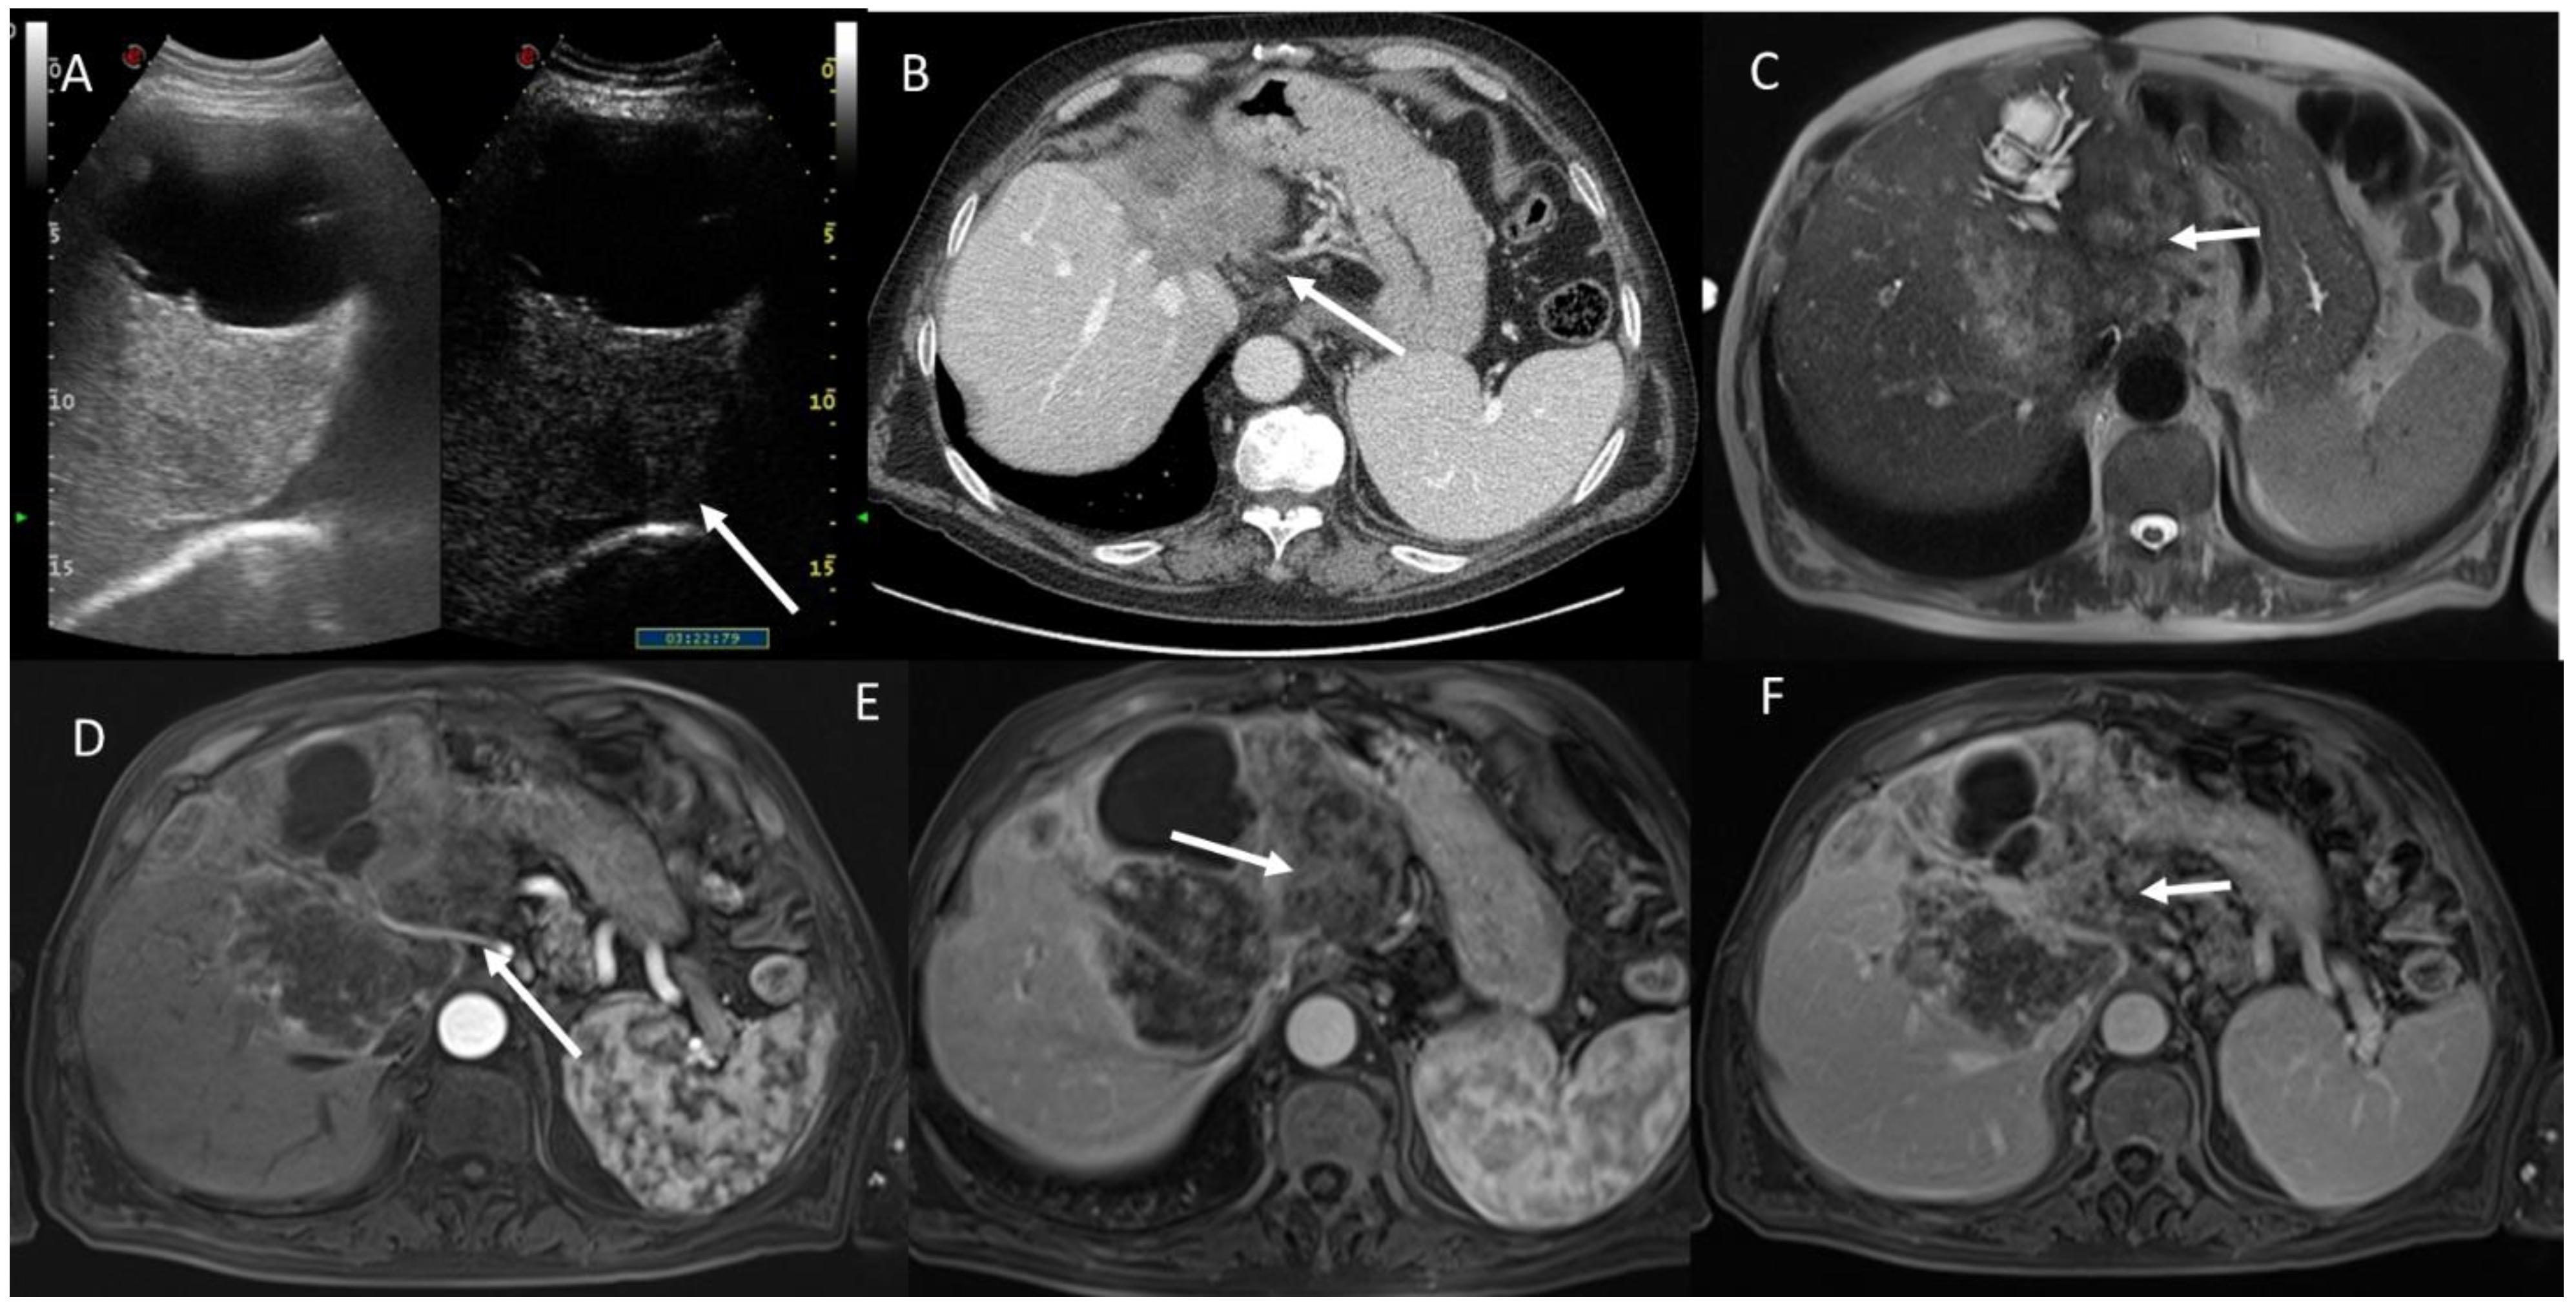

4. Fibropolycystic Liver Disease

6.2. Intraductal Papillary Neoplasia of the Bile Duct

6.3. Intraductal Tubulopapillary Neoplasms of the Bile Duct

6.4. Hepatobiliary Mucinous Cystic Neoplasm

6.5. Diagnostic Management

- Granata, V.; Fusco, R.M.; Catalano, O.; Filice, S.; Avallone, A.; Piccirillo, M.; Leongito, M.; Palaia, R.; Grassi, R.; Izzo, F.; et al. Uncommon neoplasms of the biliary tract: Radiological findings. Br. J. Radiol. 2017, 90, 20160561. [Google Scholar] [CrossRef] [PubMed]